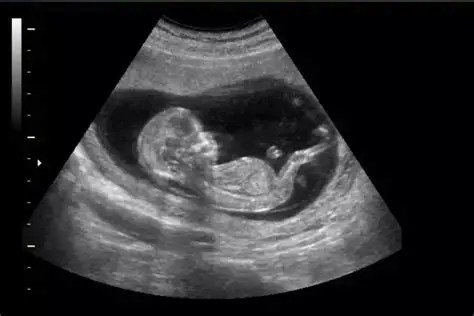

- Ecografía Morfológica: Se realiza entre las semanas 19 y 21.6 para evaluar el desarrollo del feto y detectar posibles anomalías estructurales.